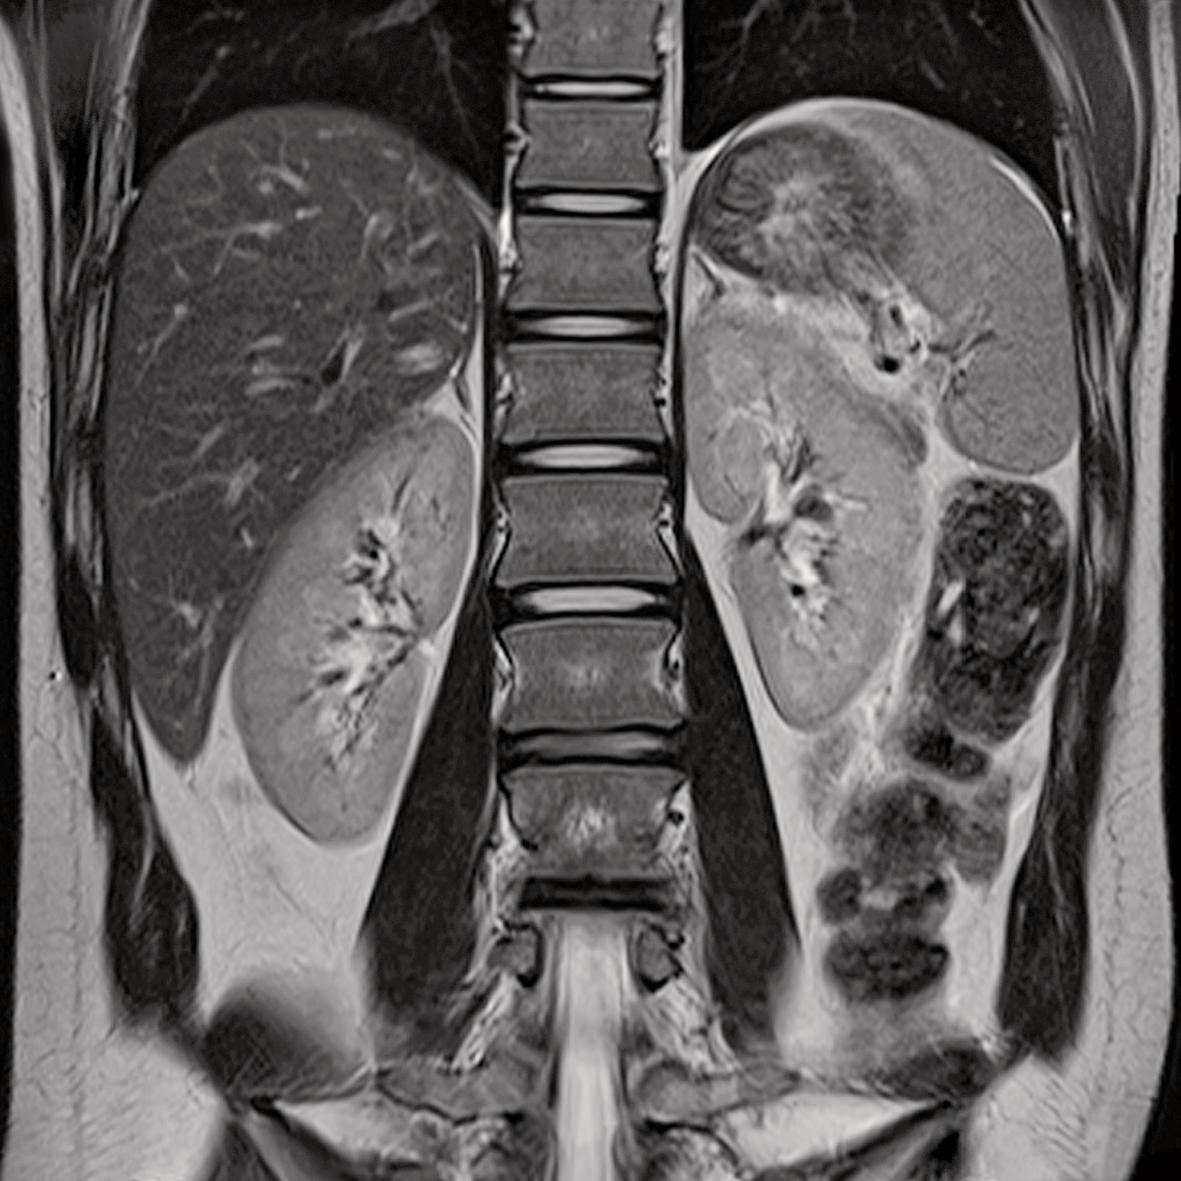

Coronal Mri Abdomen . More so than musculoskeletal and brain mri, body mri is confounded by protocols of varying design and quality (1). This handout explains how an mri scan of the abdomen works, how it is done, how to prepare for it, what to expect during the scan, and how to. Normal abdominal mr imaging study. The timing of radiofrequency pulse sequences used to make. Use the mouse scroll wheel to move the images up and. Normal appearance of liver, gallbladder, spleen, pancreas, kidneys, adrenals,. Citation, doi, disclosures and article data. Mri coronal cross sectional anatomy of abdomen. Body mri is a cornerstone of abdominal imaging and a key tool for problem solving, diagnosis, monitoring of treatment response, and surveillance. This article lists a series of labeled imaging anatomy cases by body region. This mri abdomen coronal cross sectional anatomy tool is absolutely free to use.